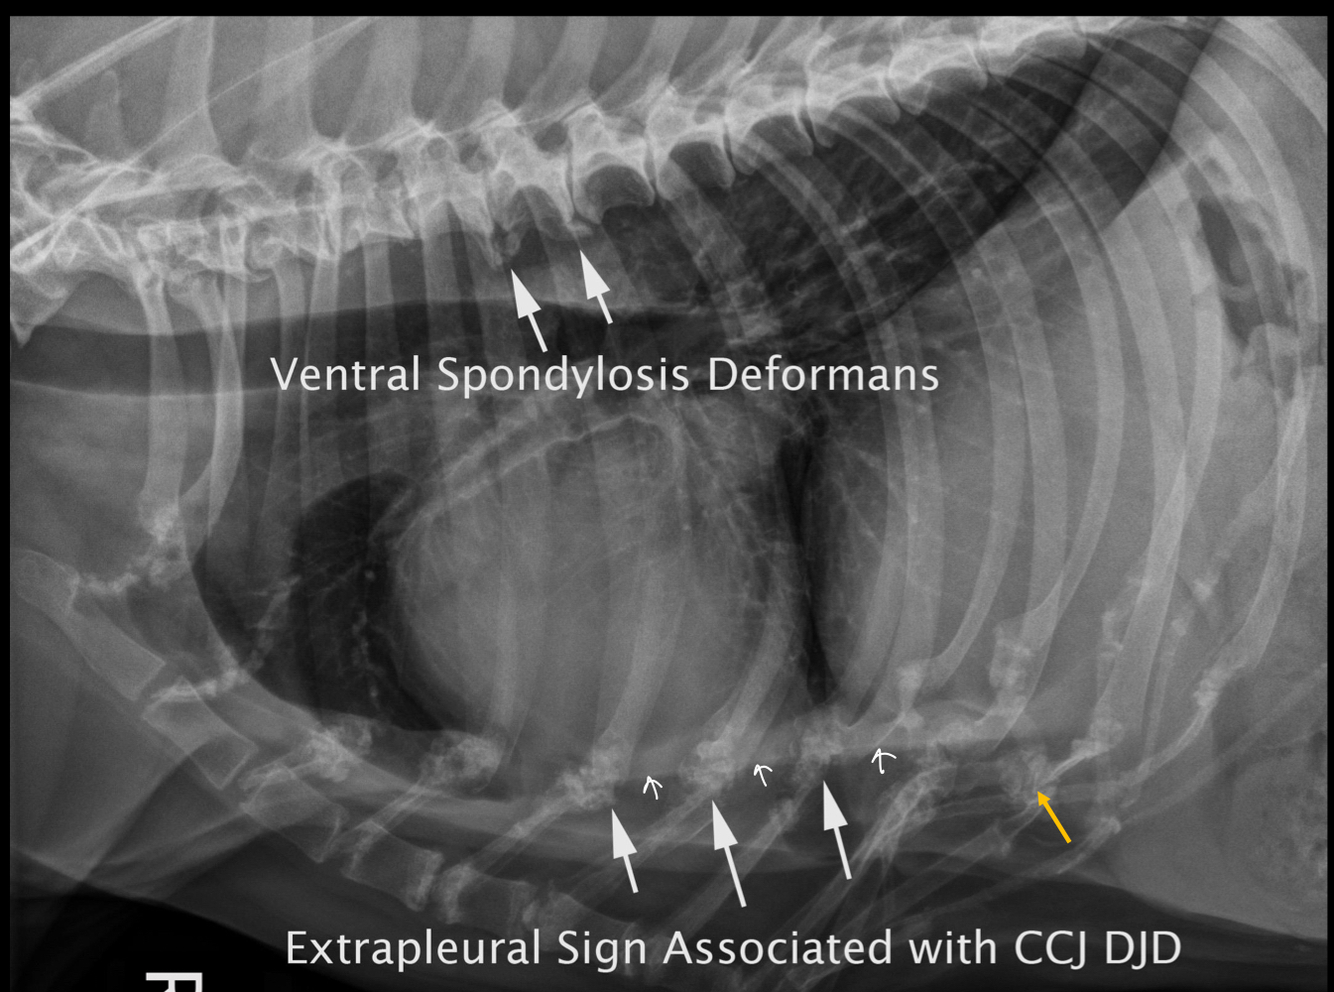

Thoracic spine, ribs, and sternum:

A

• VSD: osseous formation on ventral vertebral bodies

• ventral radiopaque line secondary to rib/costal cartilage degeneration

• costal cartilage fracture and callus formation